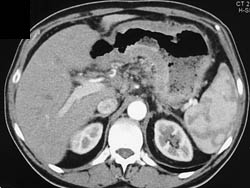

Diagnosis

Antral Cancer